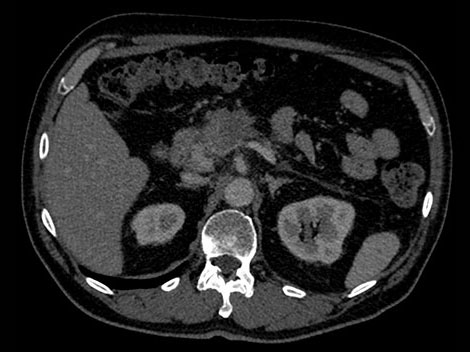

Возраст: 50 Рост: 1,80 см Вес: 75 кг КТ-ангиография брюшной полости при 70-секундной задержке введения контрастного вещества

В рассматриваемом гипотетическом случае рентгенологам требуется больше информации о подозрительном образовании в поджелудочной железе. Для постановки точного диагноза необходимо определить его материальный состав.

Обычно, если полученные КТ-изображения не дают однозначной информации, пациенту может быть назначена повторная процедура.

В отличие от стандартных, изображения, полученные с помощью системы IQon Spectral CT, всегда несут спектральную информацию — для этого не требуется планирования специального режима исследования и дополнительных настроек. Таким образом, пользователь может выполнять анализ спектральных данных любого изображения в ретроспективном режиме с помощью различных инструментов просмотра. К примеру, всегда можно выбрать моноэнергетический уровень или вычленить данные о составе тканей. Попробуйте сами.